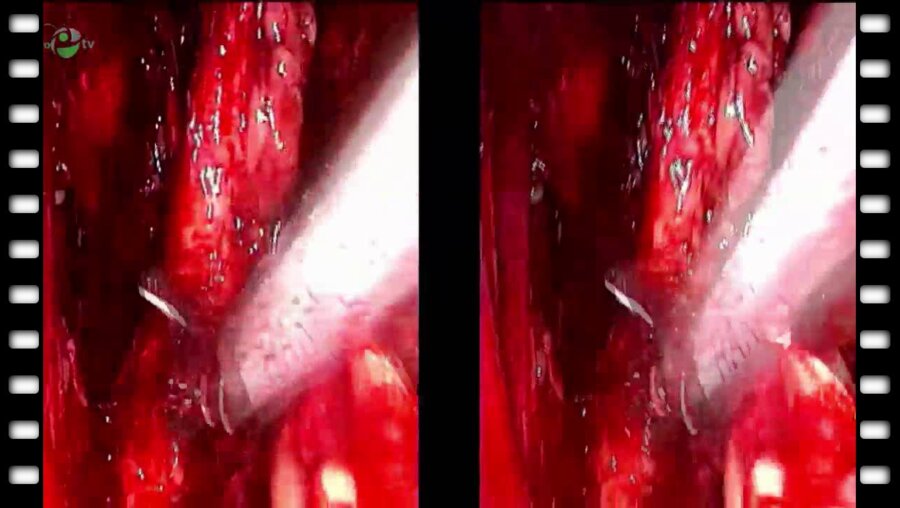

Мастер-класс с международным участием «Техника миниинвазивной радикальной простатэктомии»

Россия, Краснодар

29 апр 2014

3660 просмотров